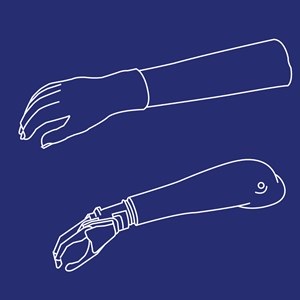

Kosmetisk/æstetisk armprotese

Type: pdf

Størrelse: 1513 KB

Mekanisk konventionel armprotese

Type: pdf

Størrelse: 1150 KB

Myoelektrisk armprotese

Type: pdf

Størrelse: 746 KB